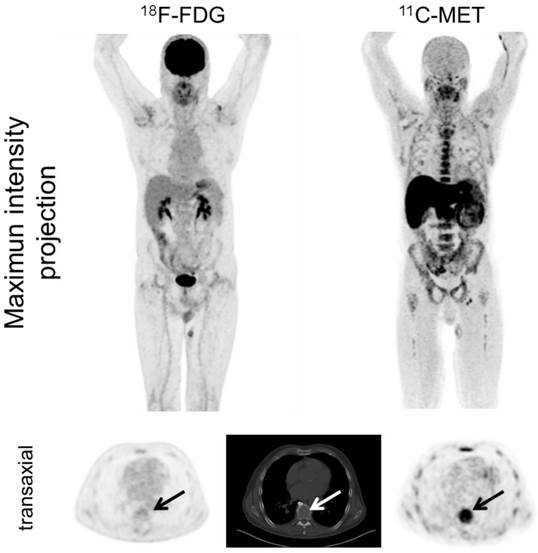

In PET/CT examinations with MET, MM lesions were detected in 39/43 subjects (90.7%). In contrast, FDG did not identify any focal lesions in 10 patients (FDG-positive lesions in 33/43 patients, 76.7%; p<0.05; figure 1). The case presenting with solitary plasmacytoma was identified by PET using both tracers.

Display of a patient (patient #11) with a history of Ig G λ MM after autologous stem cell transplant who was referred due to still low but rising serum free light chains. Whereas PET/CT with FDG did not depict hypermetabolic intra- or extramedullary foci suspicious for active MM, MET demonstrated inhomogenous, focally increased tracer uptake of the axial (transaxial slice of thoracic vertebra Th 8, arrows) as well as appendicular skeleton (maximum intensity projection). Bone marrow biopsy confirmed low tumor cell burden of 5%.

Additionally, MET identified extramedullary lesions in 12/43 patients (27.9%), whereas FDG recorded 10/43 patients with EMD (23.3%). Lymph node involvement was most commonly seen (7/43 [MET] vs. 6/43 [FDG]), followed by manifestations in soft tissue (6/43 [MET] vs. 4/43 [FDG]), and lungs (2/43 [MET] vs. 2/43 [FDG]). Regarding intramedullary MM, MET revealed involvement of the appendicular skeleton in 37/43 patients (86.0%), whereas 9 cases were missed with FDG (FDG-positive lesions in 28/43 patients, 65.1%) (supplementary table 3).